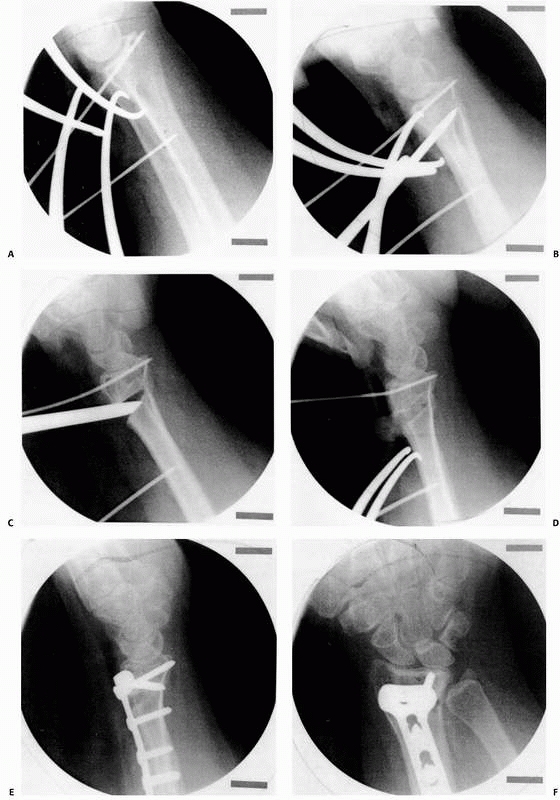

![]() |

FIGURE 30-24

The fracture has been overreduced with excessive palmar tilt. This can be prevented by use of the fluoroscope and adjustment of the external fixator. |

FIGURE 30-25 A. Typical three-part intra-articular fracture of the distal radius. B. Depression of the lunate facet palmarly is difficult to reduce by closed methods. C. A plate applied palmarly to the lunate facet reduces and mortars both the DRUJ and the radiocarpal joint.

|